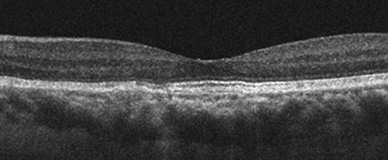

황반변성

정상안